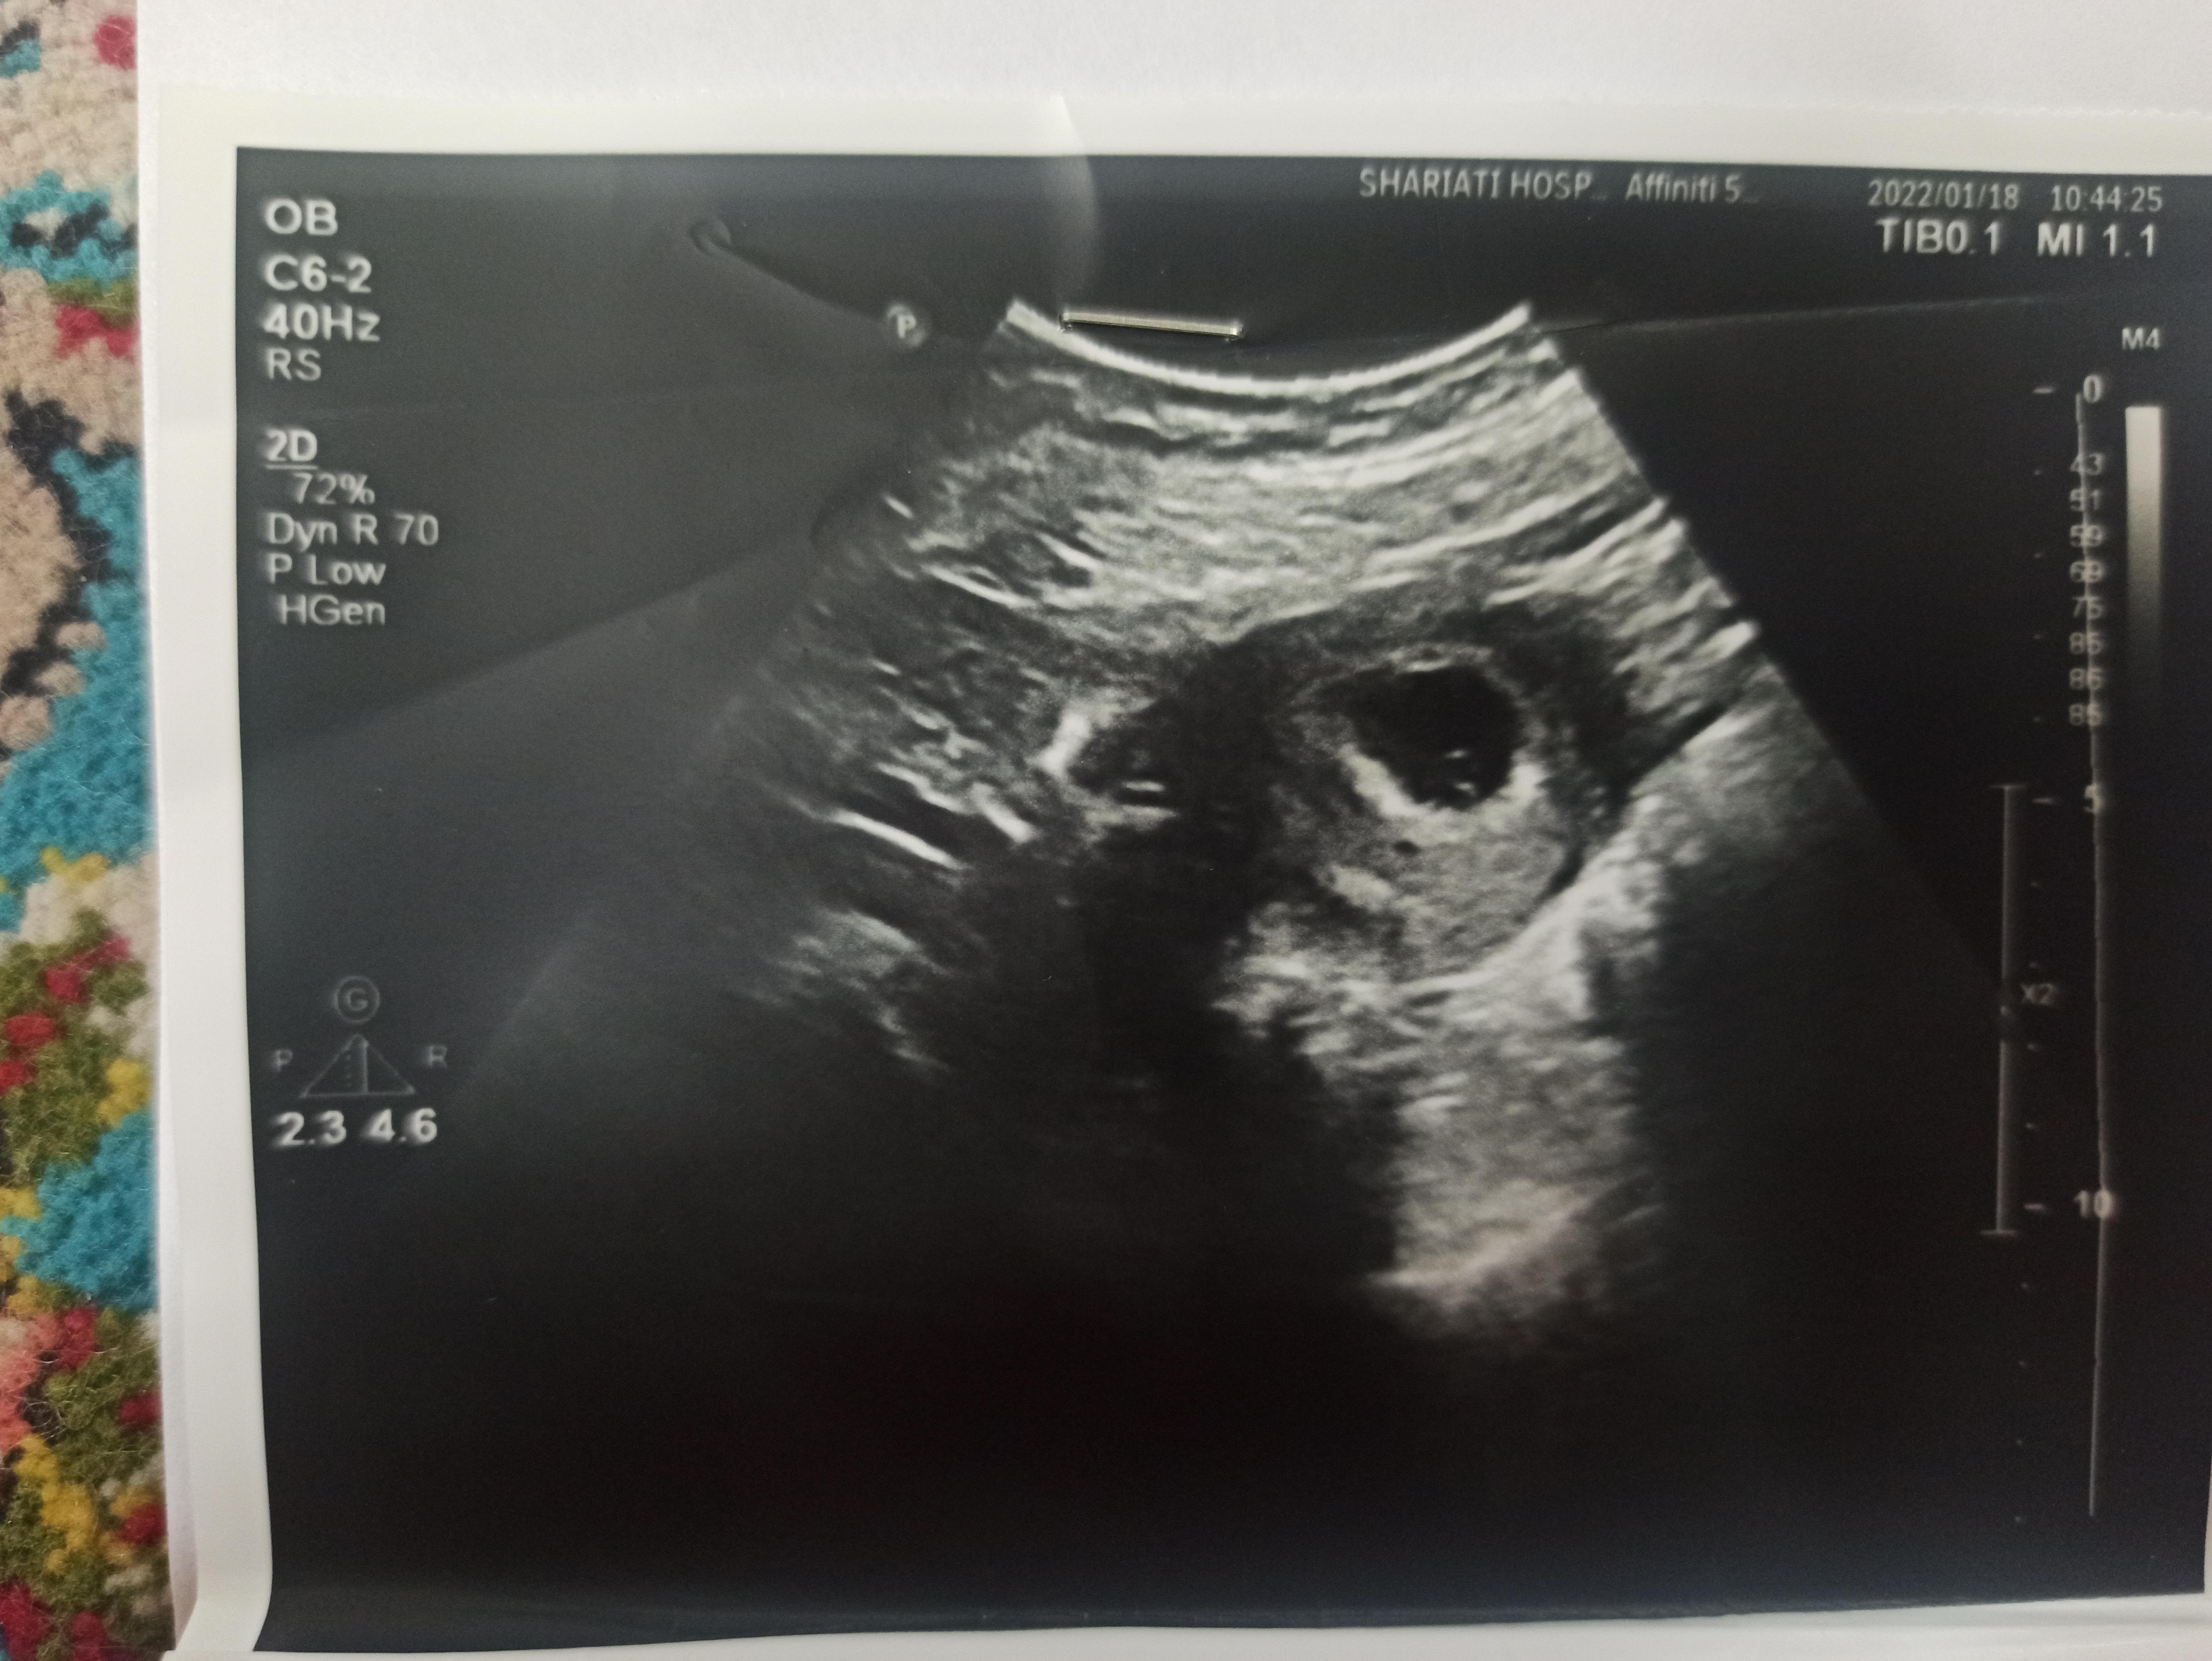

roomoo عضویت: 1398/12/05 تعداد پست: 2589 اجی درست شد الان از کدوم سنو بدم از سونو زیر ده هفته بده گلم تماشا کردن شغل دوم اکثر ماهاست؛البته اگر قضاوت کردن را شغل اول مان حساب کنید

roomoo عضویت: 1398/12/05 تعداد پست: 2589 عزیزم دختره تماشا کردن شغل دوم اکثر ماهاست؛البته اگر قضاوت کردن را شغل اول مان حساب کنید